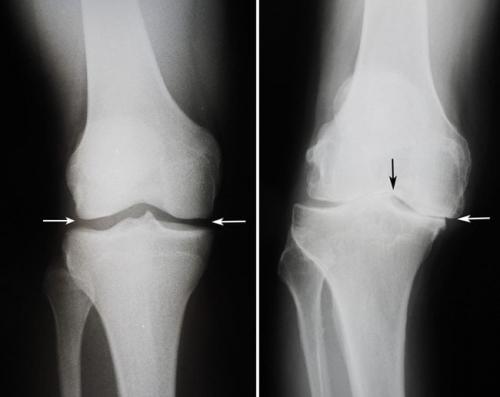

Для диагностики начального артроза коленного сустава могут применяться рентгенография, магнитно-резонансная томография и артроскопия.

Кроме этого, существует три степени тяжести такого патологического процесса. При первой степени клинические проявления имеют минимальную степень выраженности, деформации отсутствуют. Вторая степень характеризуется усилением симптоматики, умеренным ограничением движений в суставе. При третьей степени определяется заметная деформация сустава.